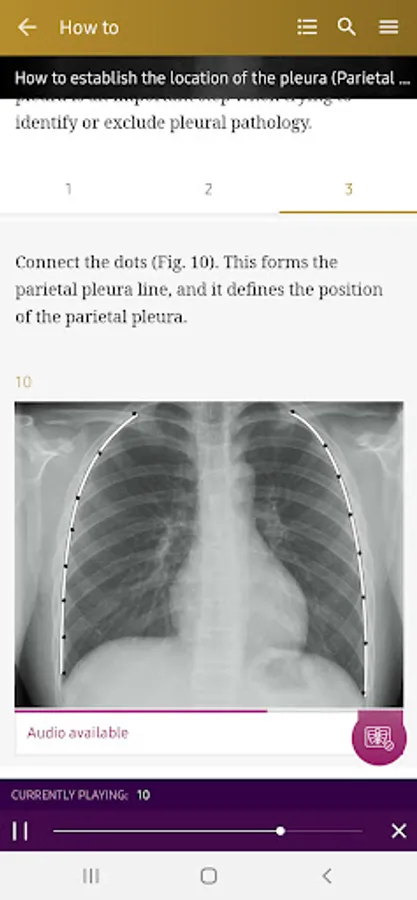

How To’s – 34 step-by-step guides, with annotated x-rays, to illustrate key skills needed to confidentially interpret chest x-ray.